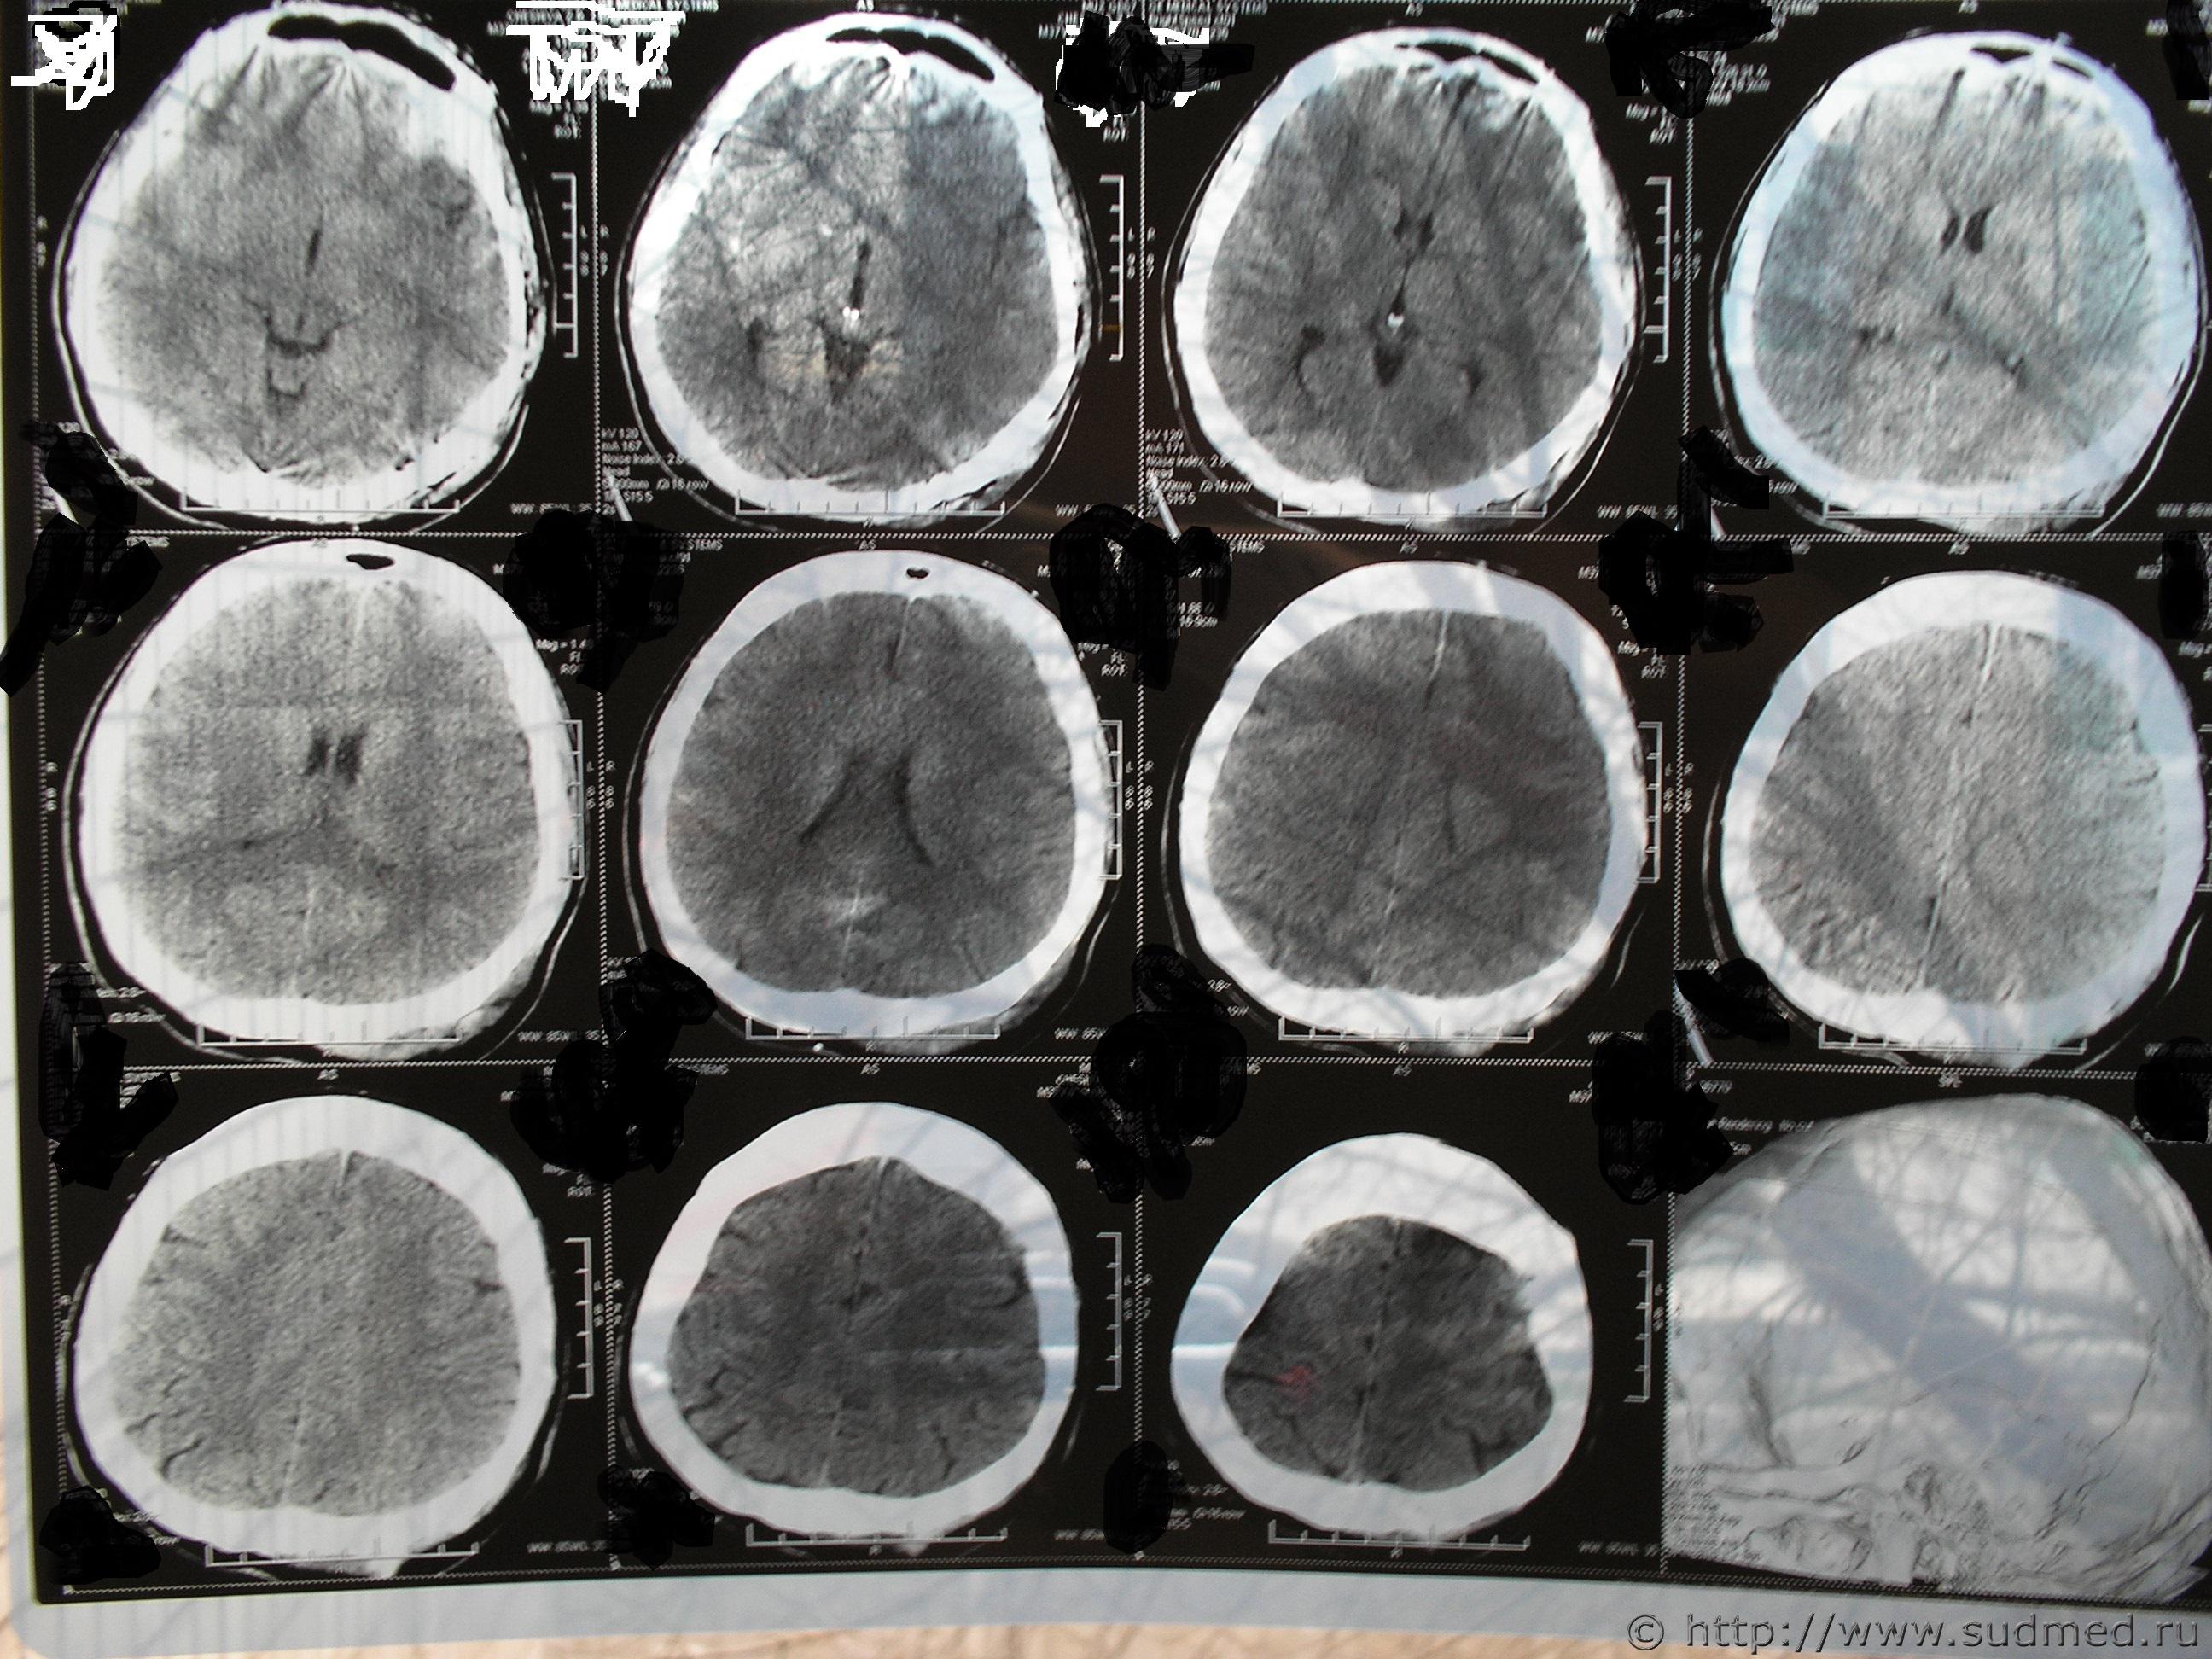

Нужно знать, что видно на данных снимках КТ. Спорная экспертиза. Делали по копии мед. карты и по этим снимкам. Снимки на руках у потерпевшего, еле достали. Исчез рентген потерпевшего из приемного отделения, осталась только запись в карте. Повреждений свода черепа не обнаружено. Диагноз в обвинении - Комплексный перелом свода и основания черепа, отоликворея слеа, УГМ средней тяжести, субарахноидальное кровоизлияние, пневмоцефалия, алкогольное опьянение, ушибленная рана на затылке. Потерпевший выписан из больницы на 18й день, более нигде не наблюдался. Говорит лечится в частном порядке. Мнение эксперта-рентгенолога - перелом клиновидной кости давностью не более 6-8 недель. А снимки сделаны в первые сутки. Есть еще пара снимков, но такого же качества и, как написано в экспертизе дополнительной информации не содержат. Очень нужно знать, что на снимках, независимое мнение. Есть еще снимок МРТ через три месяца. Информацию на дисках не предоставили.

Проконсультируйтесь с опытным рентгенологом, специалистом по КТ. Лучше - с двумя-тремя. Это придется сделать очно, т.к. информация существенно теряется: а) при перефотографировании пленок КТ, б) при пересылке через интернет этих фотографий. Полагаю, что приватным образом такую консультацию можно получить у любого подобного специалиста. Получить какое-то письменное заключение возможно при оформлении договорных отношений на кафедре рентгенологии мед.ВУЗа, в мед.центре, профилирующемся на КТ диагностике и т.д. Лучше представить ВСЕ снимки КТ (тогда более достоверно и аргументированно можно судить о динамике изменений, о давности травмы), все КТ на цифровом носителе (можно будет построить 3D-реформацию изображения, т.е. более детально определить распространение перелома).